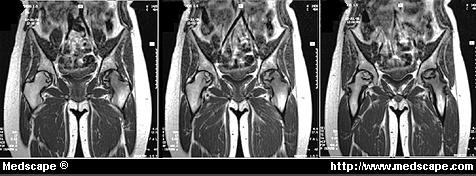

Figure 4. MRI showing juxta-articular avascular osteonecrosis of the hip. Reprinted with permission from the Virtual Hospital. La MRI mostra osteonecrosi avascolare vicino all’articolazione dell’anca.

La risonanza magnetica (Magnetic resonance imaging – MRI) (Fig.4) riesce ad individuare precocemente le lesioni, ma costosa generalmente non rientra tra gli esami di screening per una ampia popolazione. Fu usata nel 1981 dal Decompression Sickness Registry, il quale ha rilevato che la percentuale di necrosi, sia articolare che ossea, aumenta in un campione di subacquei con l’età e con l’esperienza.